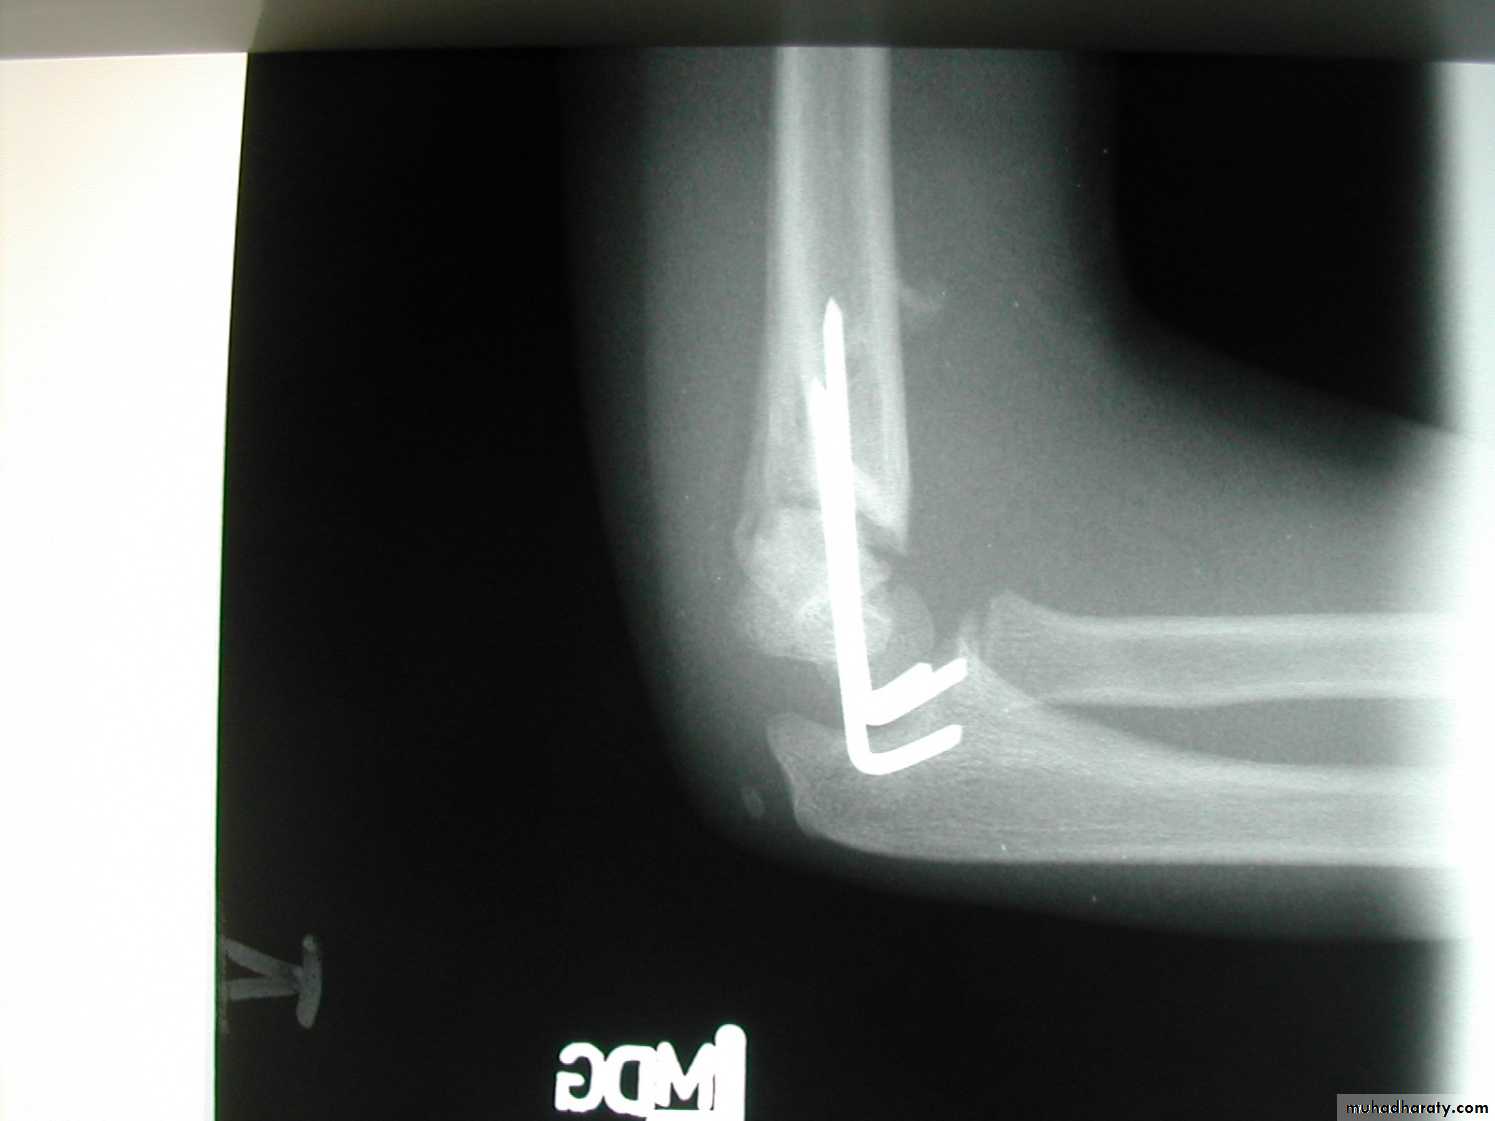

Injury film

3 wks post fracture

fat pads displaced

Type I suspectedPeriosteal new bone

The original suspicions of

a fracture are now confirmed.